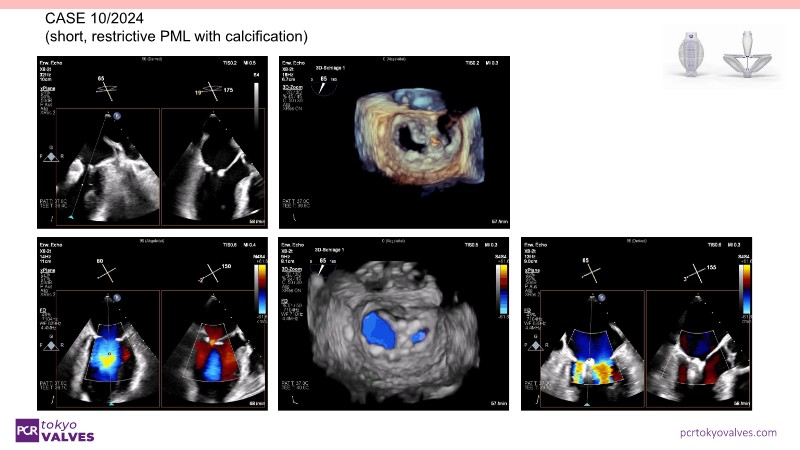

Through case reviews, explore the latest advancements in transcatheter edge-to-edge repair (TEER) for degenerative mitral regurgitation. Discover how a novel TEER device expands treatment possibilities, offering predictable and durable results.